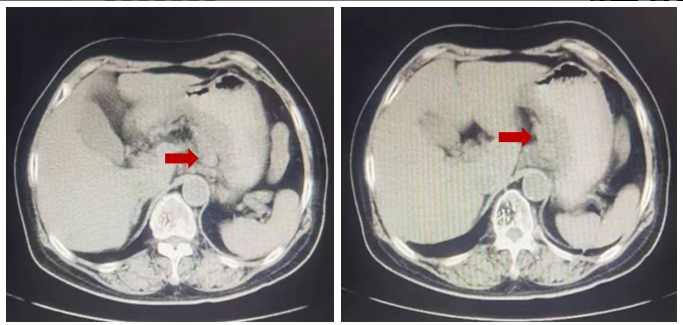

2023年8月10日复查CT示肝脏靶病灶增大至48.77mm(图2)。

疗效评价为疾病稳定(SD),但有进展趋势。

图2. 腹部CT检查(左:2023年6月27日,右:2023年8月10日)

2023年9月26日复查CT示肝脏靶病灶进一步增大至52.09mm(图3)。

疗效评价为疾病进展(PD)。

图3. 腹部CT检查(左:2023年6月27日;右:2023年9月26日)